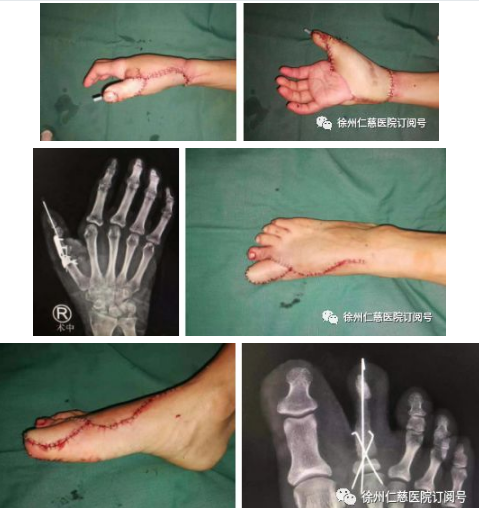

黎医生手术团队竭尽全力帮患者实现右手拇指再造。2019年7月23日,患者再次来到我院就诊。黎章灿医生组织手外科专家团队,对患者的病情进行详细讨论,最终确定了手术方案(取右足第一趾踇甲瓣+右足第二趾趾骨及关节再造右拇指指骨及拇指指间关节,取髂骨填塞右足第二趾缺损骨质)。

于7月25日,黎医生手术团队为患者进行了右拇指全型再造术。这一次手术难度最大,时间也最长。最终,经过9小时的努力,黎医生手术团队成功为患者再造右拇指!现患者再造指体已顺利成活。